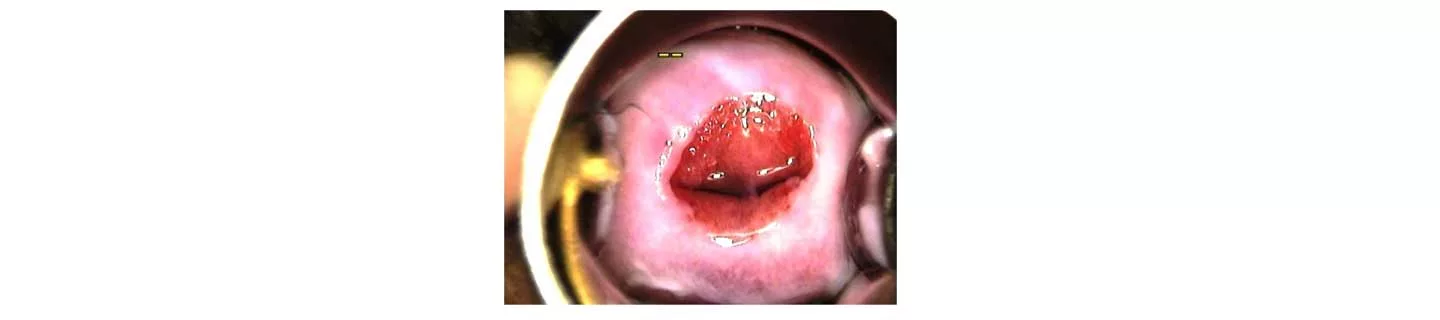

Lộ tuyến cổ tử cung là một tình trạng đơn giản, thường gặp, không gây ung thư ở phụ nữ và xảy ra khi các tuyến nằm bên trong cổ tử cung (ống cổ tử cung của tử cung) chuyển dịch quay ra ngoài làm lộ biểu mô trụ bên trong ra môi âm đạo có tính axit. Biểu mô tuyến bị lộ ra ngoài có bề mặt màu đỏ và có thể được bao phủ bởi một chất dịch màu vàng đục.

Ở phụ nữ đã sinh đẻ, biểu mô ống cổ tử cung có thể được nhìn thấy không liên tục. Lỗ ngoài cổ tử cung mở rộng và loe ra là kết quả của những thay đổi từ lần chuyển dạ và sinh trước đó.

Ở những phụ nữ đã sinh đẻ này, trong quá trình khám phụ khoa thông thường, việc đặt mỏ vịt để kiểm tra cổ tử cung có thể làm cho môi trước và môi sau cổ tử cung tách ra, để lộ biểu mô trong ống tuyến cổ tử cung. Khi bác sĩ rút mỏ vịt ra, hai môi trước và sau cùng khép lại, và thường thì vùng lộ tuyến cổ tử cung cũng biến mất.

Lộ tuyến cổ tử cung không cần phải điều trị ngoại khoa trừ trong một vài trường hợp hiếm gặp như xuất tiết chất nhầy quá mức, thường xuyên ra máu giữa chu kỳ kinh hoặc ra máu sau quan hệ tình dục, những điều này gây khó chịu cho phụ nữ. Trong những trường hợp như vậy, bệnh ác tính nên được loại trừ bằng PAP – smear hoặc soi cổ tử cung và bệnh viêm nhiễm có thể được kiểm tra bằng xét nghiệm cấy dịch âm đạo trước khi thực hiện bất kỳ điều trị nào.